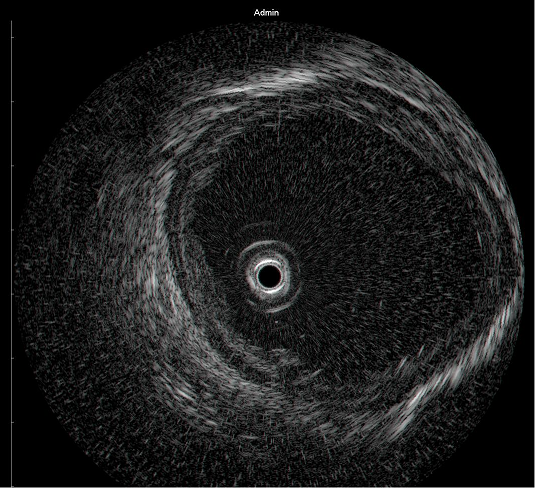

超声内镜下 食管肿瘤影像